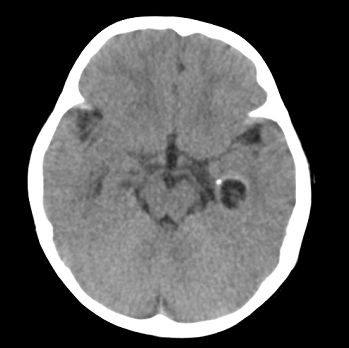

以下是引用22222222在2008-6-9 21:03:00的发言:[br]病灶周围见脑组织包绕,上部可见等或稍高密度壁环绕,壁且见小点钙化-----考虑皮样囊肿或表皮样囊肿可能,但侧脑室颞角内病灶不排除.